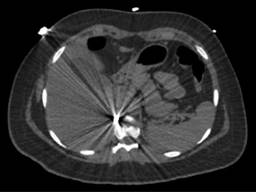

En la exploración física, sus signos vitales fueron los siguientes: frecuencia cardiaca: 74 latidos/minuto; tensión arterial: 98/67 mmHg; frecuencia respiratoria: 19/minuto, temperatura de 36 oC y saturación de oxígeno: 98%. En tórax presentaba un orificio de entrada de PAF en el cuadrante superior externo de la mama derecha (Figura 1), los campos pulmonares estaban bien ventilados. El abdomen era plano, con peristalsis, blando y sin dolor a la palpación. La biometría hemática reportó lo siguiente: hemoglobina: 12.8 g/dl, hematocrito 36.4% y leucocitos: 6,400/ml. La radiografía de tórax descartó neumotórax (Figura 2). Una TC de tórax y abdomen mostró un cuerpo extraño metálico alojado en la línea parasagital derecha a nivel de la doceava vértebra torácica (Figura 3), sin lesión pulmonar ni diafragmática (Figuras 4 y 5); en abdomen se observó un trayecto por PAF con lesión hepática grado IV de 12 cm por 2.3 cm en los segmentos IV, VII y VIII de Couinaud (Figura 5), líquido libre escaso, sin lesión de ningún otro órgano (Figuras 3, 5 y 6). Veinticuatro horas después se le realizó una TC de control, evidenciando la lesión hepática sin colección subcapsular ni extravasación activa a la aplicación del medio de contraste, sin aumento del líquido libre. Ante la correlación de estos hallazgos con la estabilidad clínica, se egresó a la paciente al cuarto día de su ingreso. Sin complicaciones un mes después de su alta.

Figura 3: Proyectil de arma de fuego alojado en la línea parasagital derecha a nivel de la doceava vértebra torácica.

Figura 5: Lesión hepática por proyectil de arma de fuego que penetra en el segmento VII y VIII y atraviesa el segmento IV de Couinaud, sin lesión diafragmática ni costal.